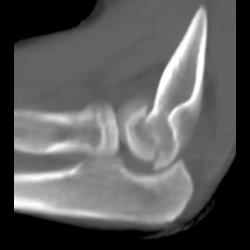

Clavicle Fracture